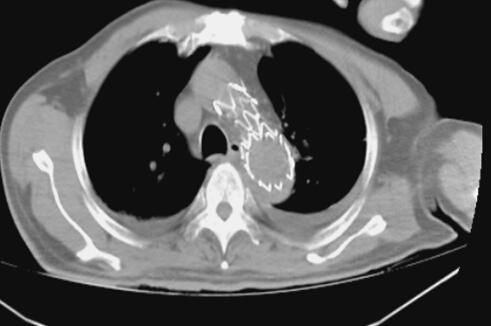

術后見支架位置良好,將破口隔絕,胸腔積液明顯減少